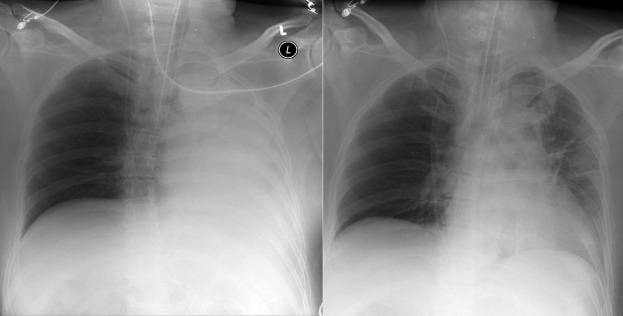

Complications of intubation ( Figs. 25-1 to 25-10 ) and ventilation that are apparent on a chest radiograph are often potentially life-threatening and should be excluded on every radiograph, both immediately following intubation and with each subsequent radiograph. These possibilities are listed in the following sections.

Right Mainstem Bronchus Intubation

- □

Location of the tip of the ET tube

Possible overinflation of the right lung

Possible volume loss of the left lung